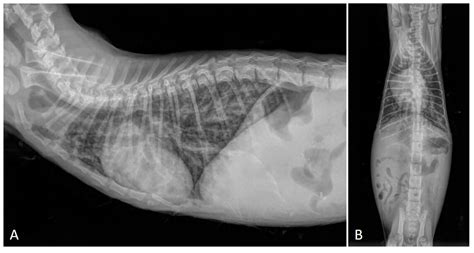

• Radiographs (X-rays): Chest X-rays can reveal inflammation, fluid, or other abnormalities in the lungs.